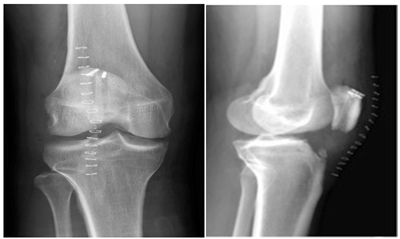

GC, a 38-year-old male, presented to the emergency room with complaints of right knee pain. The patient admitted to landing awkwardly one day ago while playing basketball and heard a popping sound that he localized to the right knee. He had immediate pain and swelling and was unable to bear weight. On exam, he had a palpable defect in his patellar tendon and was unable to straighten his leg against gravity. He was evaluated with x-rays (Figures 1A & 1B), which demonstrated a high riding patella. After discussing the treatment options and risks, benefits and complications of surgery, he was taken to the operating room where his patella tendon was repaired.

Figure 1 Initial injury anteroposterior and lateral radiographs demonstrating patella alta.